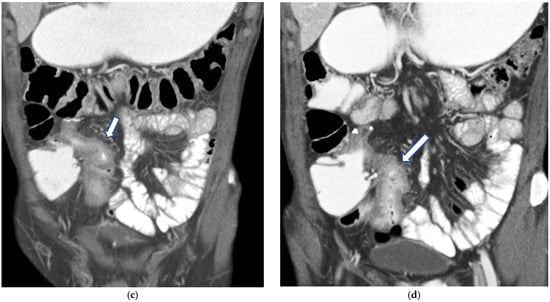

Figure 4.

(a,b) Axial CT scan in the venous phase after administration of positive oral contrast medium (Gastrografin) showing thickened terminal ileum in a 65-year-old patient with Crohn’s disease. (c,d) Coronal CT scan in the venous phase after administration of positive oral contrast medium (Gastrografin) showing thickened terminal ileum (arrows) in a 65-year-old patient with Crohn’s disease.

Figure 5.

(a,b) Coronal CT scan in the venous phase after administration of negative oral contrast medium (PEG-solution) showing thickened ileal loops (arrows) in an 85-year-old female patient with Crohn’s disease. (c,d) axial CT scan in the venous phase after administration of negative oral contrast medium (PEG-solution) showing thickened ileal loop (arrows) in an 85-year-old female patient with Crohn’s disease.